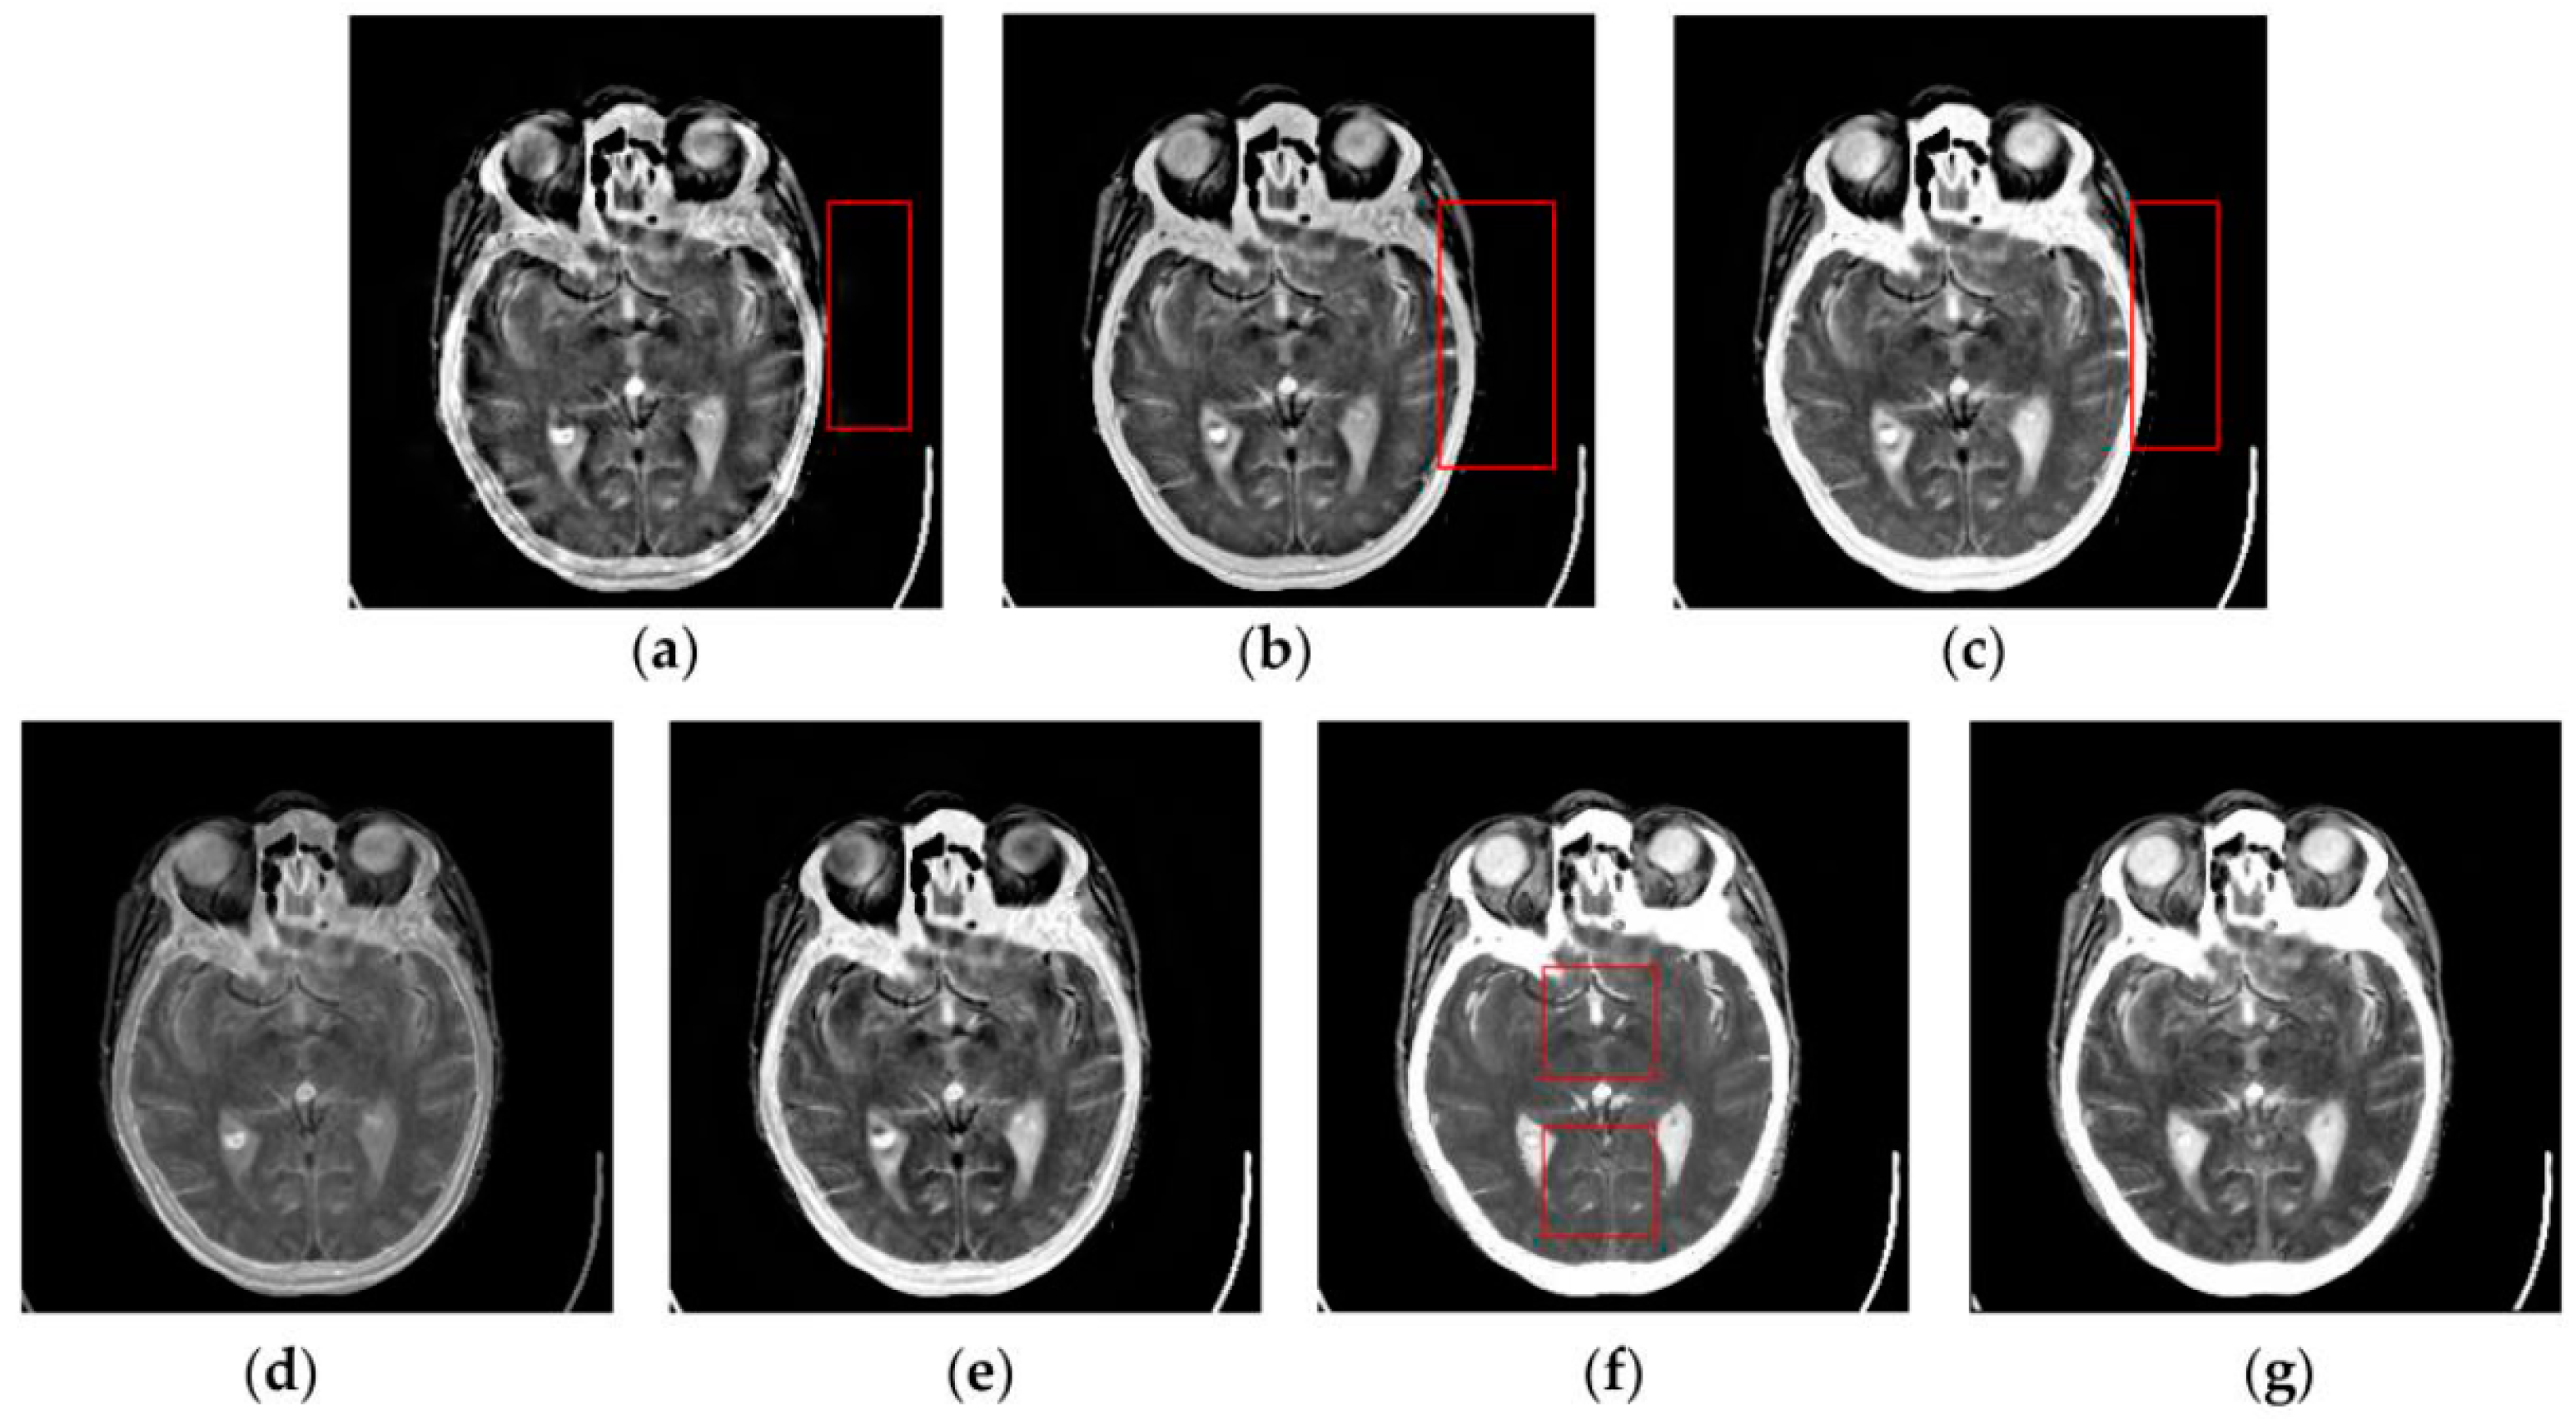

Figure 7, Figure 8, Figure 9 and Figure 10 show the fused results for the evaluated seven methods operating on such medical image pairs as Groups 1, 2, 4 and 5 shown in Figure 6, respectively. The observation from Figure 7, Figure 8 and Figure 10 shows that the DWT, NSCT and NSCT-SR methods introduce artifacts as well as false information in the fused results as indicated by the red boxes, which will greatly influence the quality of the fused images. Meanwhile, it is shown in Figure 7 and Figure 9 that the above three fusion methods cannot preserve image details well in that they produce the obvious distortion of image details marked by the red boxes in the fused results. The m-PCNN method cannot maintain the luminance of the fused results and it produces such low-contrast fused images that some important image details are difficult to identify, which is very disadvantageous for clinical diagnosis. The PCNN-NSCT method and the SCM-F method lead to loss of some important details in the source images to different extent. For example, for Groups 4 and 5, although almost all the details in the MR-T1 images can be transferred to the fused images by the PCNN-NSCT method very well, many details in the MR-T2 images have not been preserved by this method as indicated by the red boxes in the fused images shown in Figure 9e and Figure 10e. For Groups 1, 2, and 5, some image details have been seriously damaged by the SCM-F method as shown by the red boxes in Figure 7f, Figure 8f and Figure 10f.

Figure 10.

Fused results of the evaluated methods for the fifth group of source images shown in Figure 6i,j: (a) the DWT method; (b) the NSCT method; (c) the NSCT-SR method; (d) the m-PCNN method; (e) the PCNN-NSCT method; (f) the SCM-F method; and (g) the SCM-M method.

By comparison, the SCM-M method not only provides high contrast for the fused images, but also maintains important information from the various source images in the fused results effectively. In particular, the proposed method can preserve fine image details very well as shown by the red boxes in Figure 9g and Figure 10g without introducing artifacts or leading to edge blurring. The above comparisons demonstrate the superiority of the SCM-M method over other compared methods in that the fused images obtained by this method are more clear, informative, and have higher contrast.

To further verify the advantage of the proposed SCM-M method in multimodal image fusion, Figure 11 and Figure 12 show the enlarged views of fused results for all evaluated methods operating on regions of interest (ROIs) denoted by the red boxes in Groups 1 and 6 in Figure 6, respectively. Figure 13 shows the enlarged views of fused results for the proposed method, the m-PCNN method and the SCM-F method operating on ROIs denoted by the red boxes in Groups 7 and 8 shown in Figure 6. In Figure 11 and Figure 12, we can see that the SCM-M method can maintain the salient information in the source images and provide better visual perception with less loss in luminance or contrast than other compared methods. To explain this point better, some edges and regions have been chosen from Figure 11g and Figure 12g. It can be seen from Figure 11 that the SCM-M method can provide better edge preservation than all other methods as pointed by the three red arrows. Meanwhile, compared with the DWT, NSCT and NSCT-SR methods, the SCM-M method can maintain the information in the MR image shown in Figure 6f better without introducing artifacts as indicated by the two red boxes. In Figure 12, we can see that the proposed method can keep the integrity of the edge marked by the red arrow best among all evaluated methods. Likewise, as pointed by the green arrow, the edge can be preserved very well by the proposed method while it has been damaged very seriously by other methods. Besides, the sharpness of the region shown by the red box can be maintained by the proposed method better than by the compared method. Furthermore, it can be seen in Figure 13 that compared with the m-PCNN and SCM-F methods, the SCM-M method can preserve fine image details and maintain image contrast better.